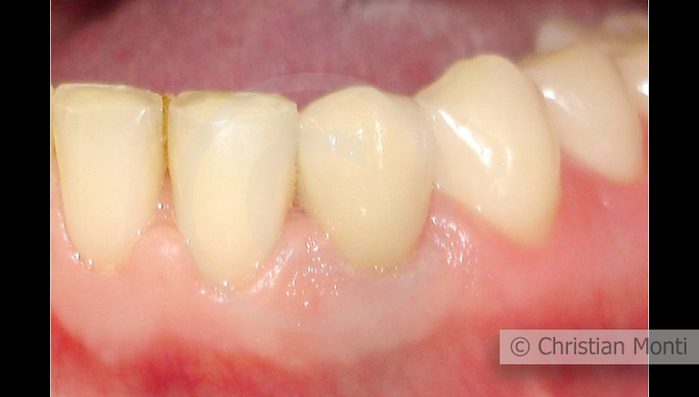

EDENTULIA SINGOLA

Impianto in sostituzione di un canino deciduo